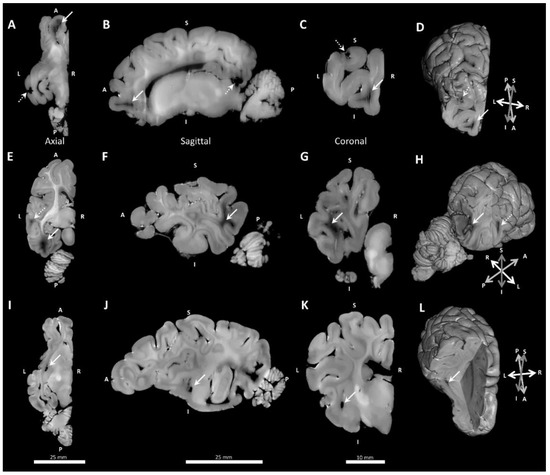

2.4.4. Gross Anatomical Measurements